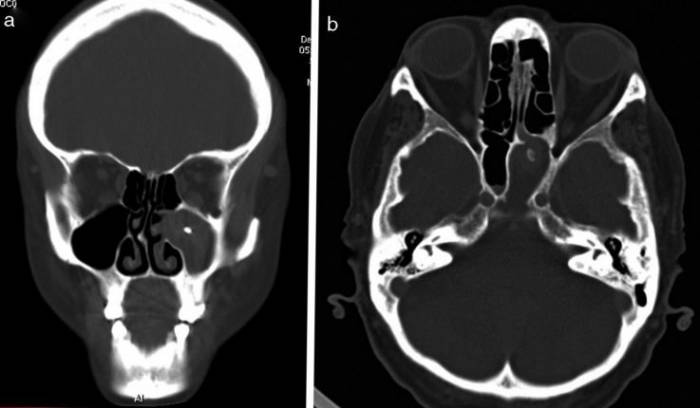

- Заблокированные дренажные пути могут быть вызваны аномалией структуры пазух носа и носовых раковин, включая искривление носовой перегородки, что может быть обнаружено при проведении компьютерной томографии (КТ).

- Особую важность в развитии этого состояния имеет сложность анатомии и узость области среднего носового хода.

Длительное заболевание, период усиления симптомов. В правой полости носа наблюдается накопление жидкости.

Головная мигрень проявляется в области лба или за глазом. Один из симптомов — ощущение тяжести при поднятии верхнего века. Когда в процесс вовлекаются ветви тройничного нерва, боль становится острой, распространяется в область глаза и верхней части рта, и не утихает даже при приеме обезболивающих. После удаления гнойного содержимого из придаточной пазухи боли ослабевают, но через несколько часов гной снова начинает накапливаться. Для диагностики этих симптомов используются эндоскопическое исследование и КТ.